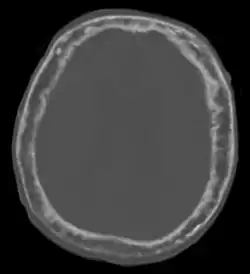

![]() CT głowy pacjenta z chorobą Pageta uwidaczniające pogrubienie pokrywy kostnej czaszki | |

Choroba Pageta kości (łac. osteitis deformans) – przewlekła choroba układu kostnego, która charakteryzuje się występowaniem co najmniej jednego ogniska nieprawidłowego tworzenia kości przez osteoblasty, poprzedzone nasiloną reabsorpcją kości przez osteoklasty.